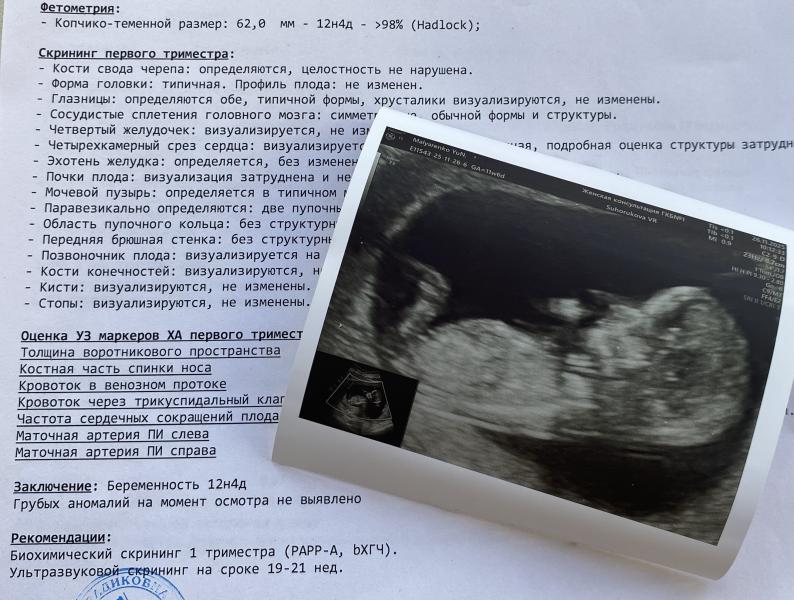

Первый скрининг при беременности: результаты и эмоции

Первый скрининг состоялся 🥰

Опережаем немного свой акушерский срок🤰🏼

В этот раз похоже носик у малыша папин 😁

У старшего на таком сроке совсем махонький был. Всё у нас хорошо 🙏🏻 Слава Богу! ❤️